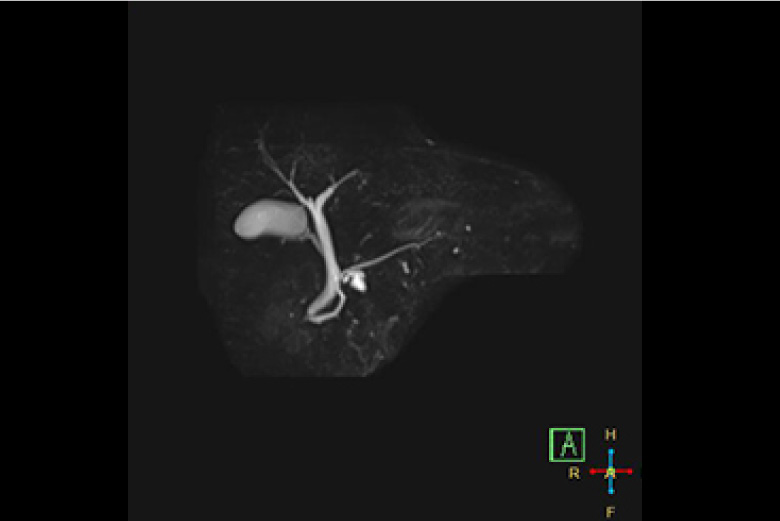

MRI(磁気共鳴画像)

MRIとは、Magnetic Resonance Imaging の略で磁気共鳴断層撮影装置と呼ばれ、強い磁場の中で、人体内の水素原子核に電波を与え、そこから発生した電波を受し画像化する検査です。

MRIは、X線撮影(一般撮影・CT)では描出できない脳・脊髄・椎間板・半月板・筋肉・腱・血管などの描出に優れています。また、人体の様々な断面像が得られるのと同時にX線を使わないため被ばくの心配がありません。

急性期の脳梗塞の診断に優れ、脳外科領域において非常に有用な検査です。軟部組織のコントラストに優れ、外科・整形外科・婦人科・泌尿器科の検査に有用です。

認知症や脳動脈瘤の診断など、検診等にも有用です。

造影剤を使用しなくても血管画像が得られる為腎機能が悪い方にも有用です。

MRCP